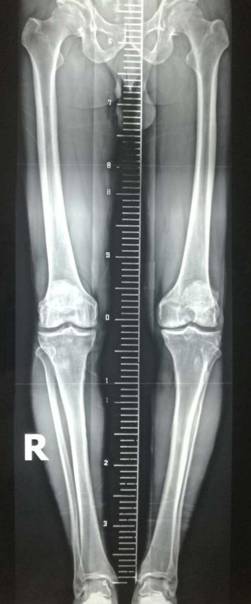

胫骨高位截骨治疗膝关节骨关节炎

优点:创伤小,疗效确切,适合生活方式活跃的年轻患者。

术前术后对比